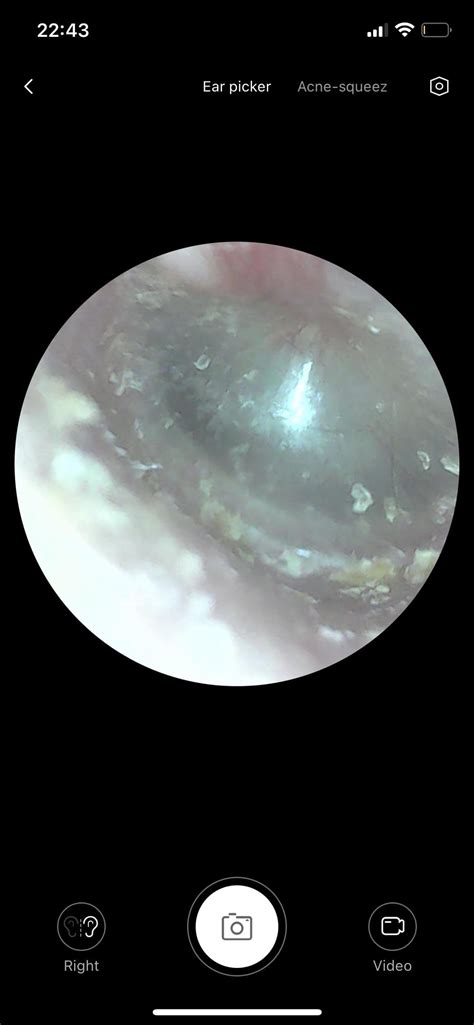

Before you attempt to remove wax, it is crucial to recognize the difference between normal accumulation and a genuine blockage. If your ear feels full, muffled, or you are experiencing mild hearing loss or discomfort, you may have an impacted wax plug. However, trying to "clean" ears that do not actually need it can lead to irritation, infection, or accidental damage to the eardrum. If you have a history of perforated eardrums, ear surgery, or currently have ear tubes, you should never attempt DIY cleaning methods and should consult an ENT specialist instead.

Once the wax has been softened, you may choose to use an ear irrigation kit. These kits typically include a bulb syringe that allows you to gently flush the ear canal with warm (body temperature) water. It is essential that the water is not too hot or cold, as this can cause dizziness or vertigo. Gently tilt your head, pull your outer ear up and back to straighten the canal, and squirt the water into the ear. Be sure to tilt your head afterward to allow all the water to drain out completely.

Sometimes, DIY methods are simply not enough, especially if the impaction is deep or the wax has become extremely hard. If your attempts to clean your ears do not improve your symptoms after a few days, or if the discomfort persists, it is time to schedule an appointment with a healthcare provider. A professional can use specialized tools, such as a microscope or a curette, to safely and quickly remove the blockage without damaging the ear canal. For many, a professional cleaning once a year is more than sufficient to maintain optimal ear health.